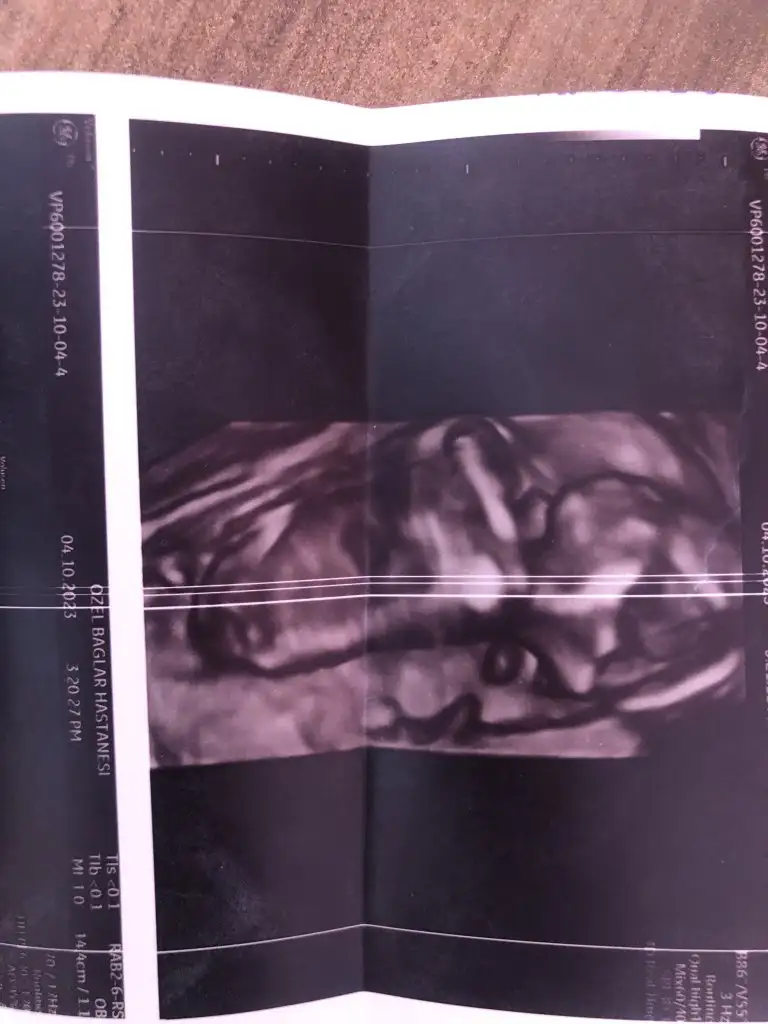

Sağlıkla gelsinBugün ki ultrason fotoğrafı

Kiz dedi doktorNeymiş cinsiyeti kuzunun

ErkkEki Görüntüle 3313896 Bana da bakar mısınız 12+3